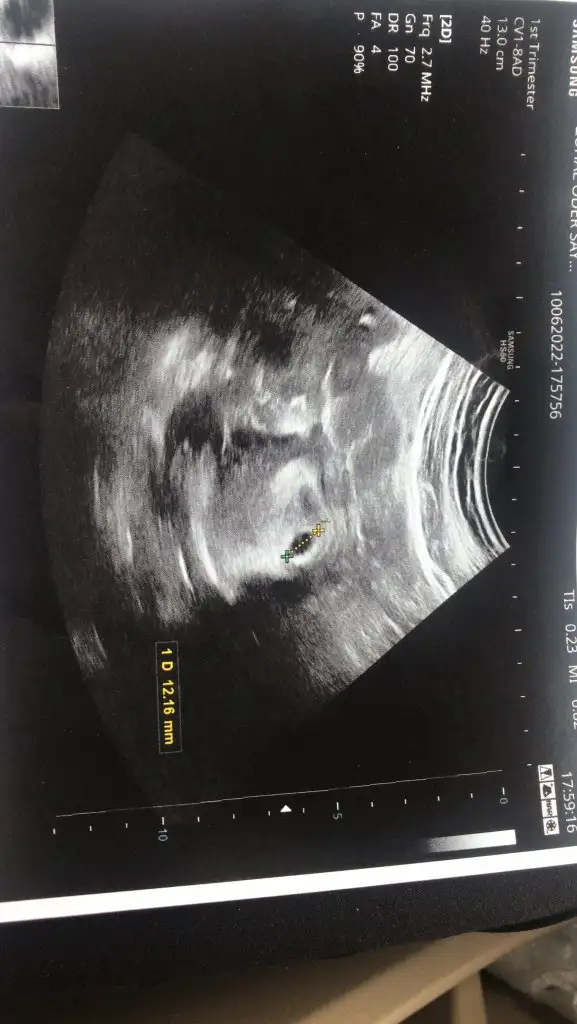

Banada bakar misiniz 7 haftalik karindan

Eklentiler

• 2DC31184-E067-4F5D-98D9-12A85D7D46A4.webp

39,6 KB · Görüntüleme: 89

Banada bakarmisiniz 7 haftalik ve karindan ultrason

• 6EE9E661-E2AF-4D3A-AE90-F2F8A72D0240.webp

39,6 KB · Görüntüleme: 77